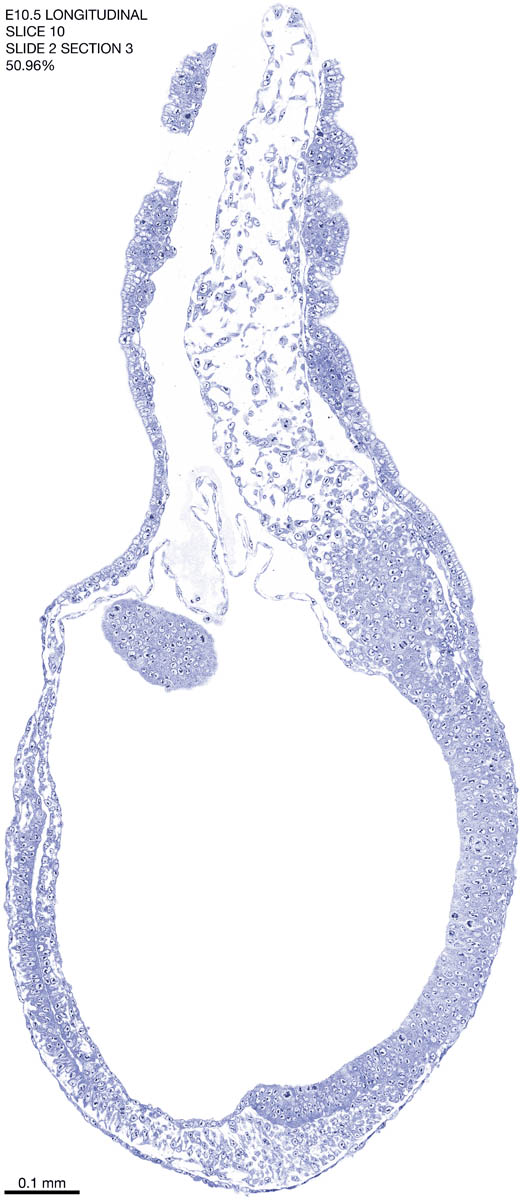

E10.5 Longitudianal Archive This page contains jpg files of ALL SLICES (each 3µm thick) that were scanned of the E10.5 longitudinally cut specimen. Download: Large | High Res Download: Large | High Res Download: Large | High Res Download: Large | High Res Download: Large | High Res Download: Large | High Res Download: Large | High Res Download: Large | High Res Download: Large | High Res Download: Large | High Res Download: Large | High Res Download: Large | High Res Download: Large | High Res Download: Large | High Res Download: Large | High Res Download: Large | High Res Download: Large | High Res Download: Large | High Res Download: Large | High Res Download: Large | High Res Download: Large | High Res Download: Large | High Res Download: Large | High Res Download: Large | High Res Download: Large | High Res Download: Large | High Res Download: Large | High Res Download: Large | High Res Download: Large | High Res Download: Large | High Res Download: Large | High Res Download: Large | High Res Download: Large | High Res Download: Large | High Res Download: Large | High Res Download: Large | High Res Download: Large | High Res Download: Large | High Res Download: Large | High Res Download: Large | High Res Download: Large | High Res Download: Large | High Res Download: Large | High Res Download: Large | High Res Download: Large | High Res Download: Large | High Res Download: Large | High Res Download: Large | High Res Download: Large | High Res Download: Large | High Res Download: Large | High Res Download: Large | High Res Download: Large | High Res Download: Large | High Res Download: Large | High Res Download: Large | High Res Download: Large | High Res Download: Large | High Res